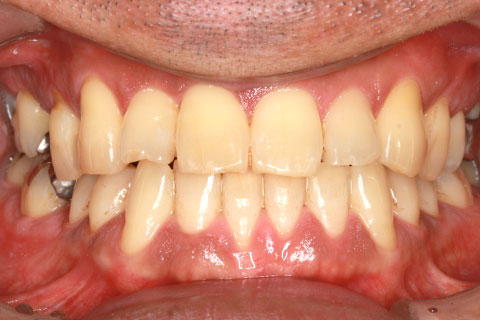

治療前

治療後

- 年齢・性別

- 23歳女性

- 治療期間

- 1年6ヶ月

- 抜歯

- 上顎4番

- 治療費

- 110万円(税込み)

- 備考

- ハーフリンガル矯正

- 治療内容

- 上下前歯部凸凹の改善

- 施術の副作用(リスク)

- 裏側矯正の特性上、表側矯正と比較すると治療期間が長くかかる場合が多い。